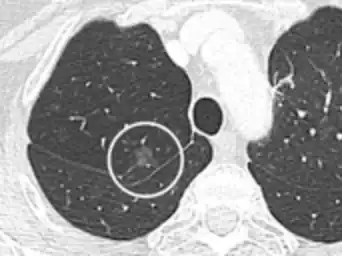

-

Low attenuating nodule (in this case a fat containing hamartoma).[9] -

Cavitation with relatively thick wall, in this case aspergilloma).[9]

- In case of calcifications, a popcorn-like appearance indicates a hamartoma, which is benign.[3]